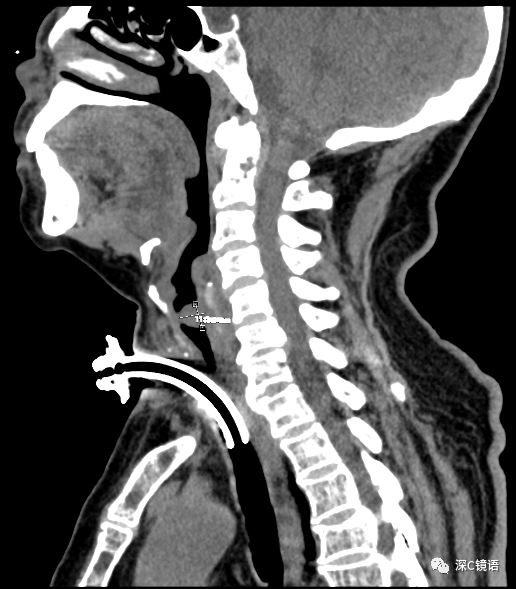

医疗方面:目前,我科室能开展呼吸内镜相关诊断与治疗技术,具体如下:诊断技术包括经支气管镜冲洗术、灌洗术、刷检术、活检术、针吸活检术、环形超声以及内科胸腔镜等;治疗技术包括球囊扩张术、支架植入术、高频电凝术、高频电圈套治疗、激光治疗、冷冻治疗、局部注药治疗等。秉承“患者所需,医者所为”的宗旨,为肺部感染、肿瘤、气道异物、不明原因胸腔积液,尤其是气道结核的患者,提供综合诊治方案。